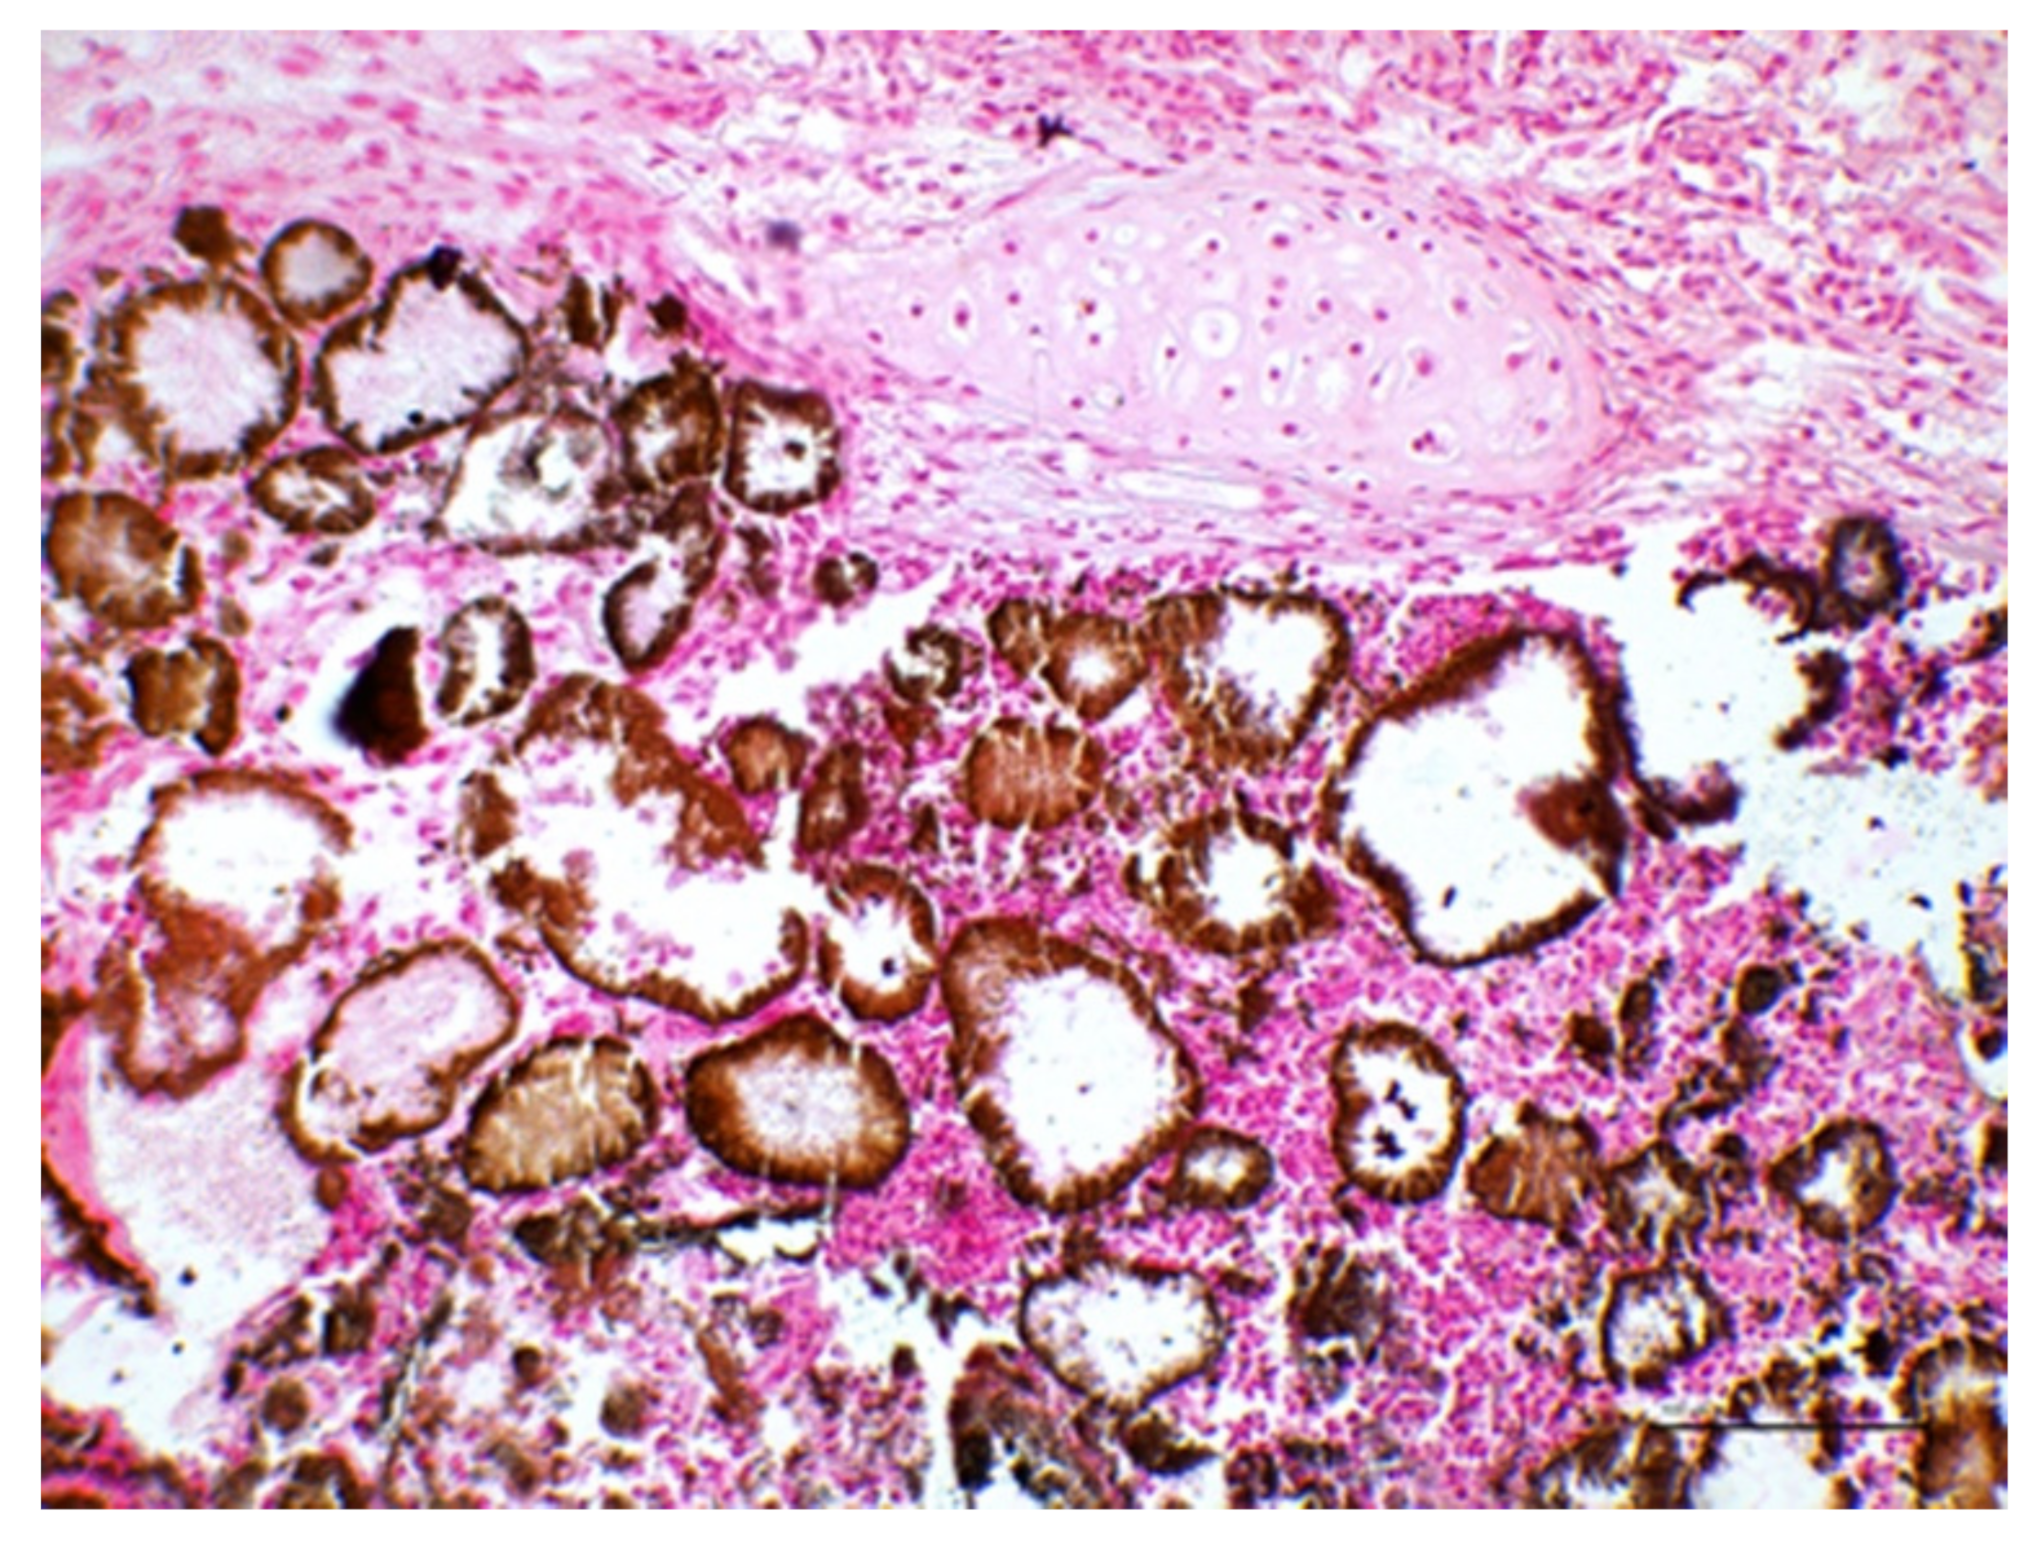

Importantly, multiple foci of mineralization were observed, scattered throughout the lung parenchyma and occasionally within the tracheal mucosa. In particular, the alveolar spaces were mainly affected, appearing as calcified casts of this portion of the respiratory tract (Figure 5).

The presence of calcium deposits was confirmed by means of the Von Kossa staining method, which was carried out on 5-μm-thick tissue sections using nuclear fast red (Bio-Optica; Milano, Italy) for counterstaining (Figure 6).

Figure 5. Lungs. The parenchyma appears widely hemorrhagic. Moreover, calcium deposits accumulate along the alveolar surface and partially obliterate the alveolar lumina (HE, magnification ×100).

Figure 6. Lungs. Calcium salt deposits appear brown-black and are abundantly accumulated within the airways, particularly along the alveolar surfaces, thereby thickening the alveolar wall and partially obliterating the alveolar lumina (Von Kossa stain, magnification ×200, bar = 100 μm).